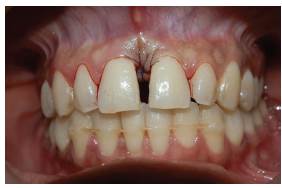

En el exámen estomatológico se observó lesión tumoral unilobular en el maxilar superior localizada a nivel de encía marginal vestibular por mesial de órgano dental 11, de base sésil, consistencia firme y blanda, de 3 mm de diámetro, de superficie eritematosa, con ligero sangrado al mínimo contacto, correspondiendo con las características clínicas descritas por Rebolledo y cols en 2015 11 (figura 1A). No se observa sobreinserción de frenillo labial superior que justifique la aparición de diastema entre los dos órganos dentarios anterosuperiores.

Se realizó evaluación de la condición de los tejidos periodontales a nivel de órgano dentario 11 mediante una sonda periodontal tipo Williams y se obtuvo profundidad de sondeo de 10 mm (figura 1B). Se evidencia margen gingival sin recesiones o hiperplasias en otras zonas; no se observa presencia de placa bacteriana abundante, cálculos supragingivales o caries que actúen como factor irritante asociado.